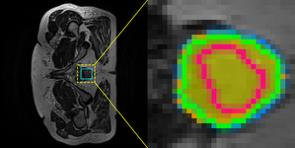

Accurate magnetic resonance imaging (MRI) segmentation is crucial for clinical decision-making, but remains labor-intensive when performed manually. Convolutional neural network (CNN)-based methods can be accurate and efficient, but often generalize poorly to MRI's variable contrast, intensity inhomogeneity, and protocols. Although the transformer-based Segment Anything Model (SAM) has demonstrated remarkable generalizability in natural images, existing adaptations often treat MRI as another imaging modality, overlooking these modality-specific challenges. We present SAMRI, an MRI-specialized SAM trained and validated on 1.1 million labeled MR slices spanning whole-body organs and pathologies. We demonstrate that SAM can be effectively adapted to MRI by simply fine-tuning its mask decoder using a two-stage strategy, reducing training time by 94% and trainable parameters by 96% versus full-model retraining. Across diverse MRI segmentation tasks, SAMRI achieves a mean Dice of 0.87, delivering state-of-the-art accuracy across anatomical regions and robust generalization on unseen structures, particularly small and clinically important structures.